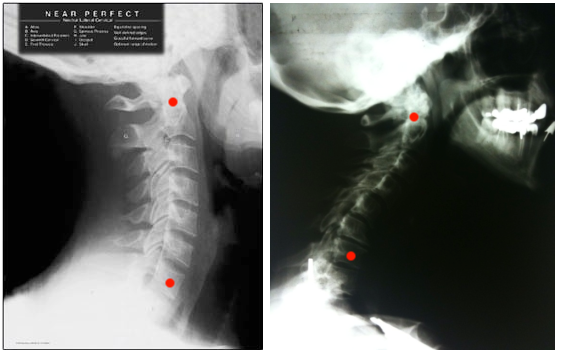

Patients often ask me, “How can I avoid neck pain?” And I tell them, “The fastest way to avoid neck pain is to stop looking